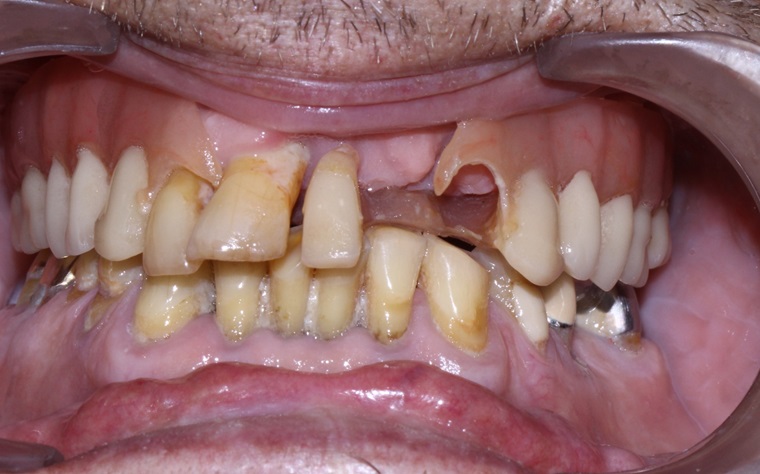

Tall and Tilted Pin Hole Immediate Loading ( TTPHIL) is a modern and most reliable technique for dental implantation. The special feature of such method is that dentist combine long and wide implants with bi-cortical support bone.

The All on 6 and All on 4 technique apply that method of implants placement.

This technique also use immediate loading so the implants are placed right after teeth extraction.

This case report show the successful All on 6 dental implantation using Alpha Dent implants.